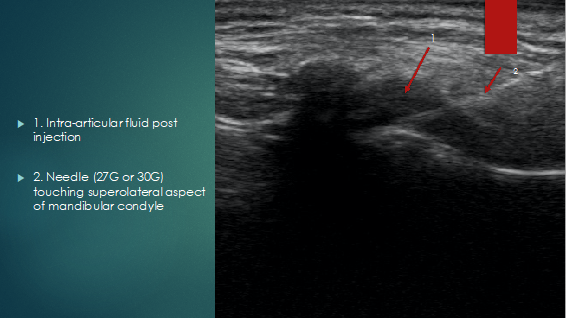

An in-plane technique is used to inject 0.5 to 0,7 ml intra-articular into the synovial pouch of the inferior joint space, with injectate filling this space, exerting effects on the synovial tissues, mandibular cartilage, and retrodiscal tissue. (Figure 5).

Figure 5: Coronal view post injection